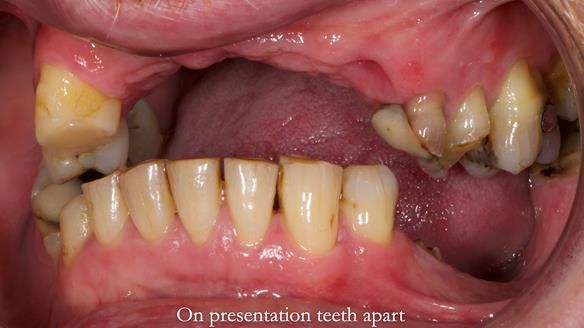

Keith’s case was one of the most challenging and rewarding cases I’ve treated this year. This 64 year old man presented with ill-fitting acrylic partial dentures that lacked stability, retention, and aesthetics. They constantly broke. He had lost the upper front teeth in a road traffic accident in his early 20s. The unopposed teeth had erupted, taking up space. After careful planning, we made a durable, metal-based upper partial denture/splint to address his dental concerns. He loved the outcome.

1. Denture design: A custom cobalt-chromium framework was Scandinavian-designed to maximise stability, protect the remaining teeth, and allow for future additions if needed.

2. Onlay preparations: Composite onlays were fitted for his upper left premolars to repair these teeth and support the new denture.

Keith’s denture incorporated a Duracetal shell clasp on upper right first premolar (Myerson), which are designed to be virtually visible, providing a more aesthetic solution while enhancing patient comfort. The Scandinavian-inspired approach, based in modern removable prosthodontic techniques, ensured the denture was not only durable but also visually pleasing. Additionally, the design was carefully planned to allow for future modifications, ensuring that if Keith loses additional teeth, the denture can be adapted rather than replaced entirely.

I also used the Dahl concept to re-establish the occlusion upon fitting the RPD, which helped to intrude the lower left canine without needing to grind it too much.